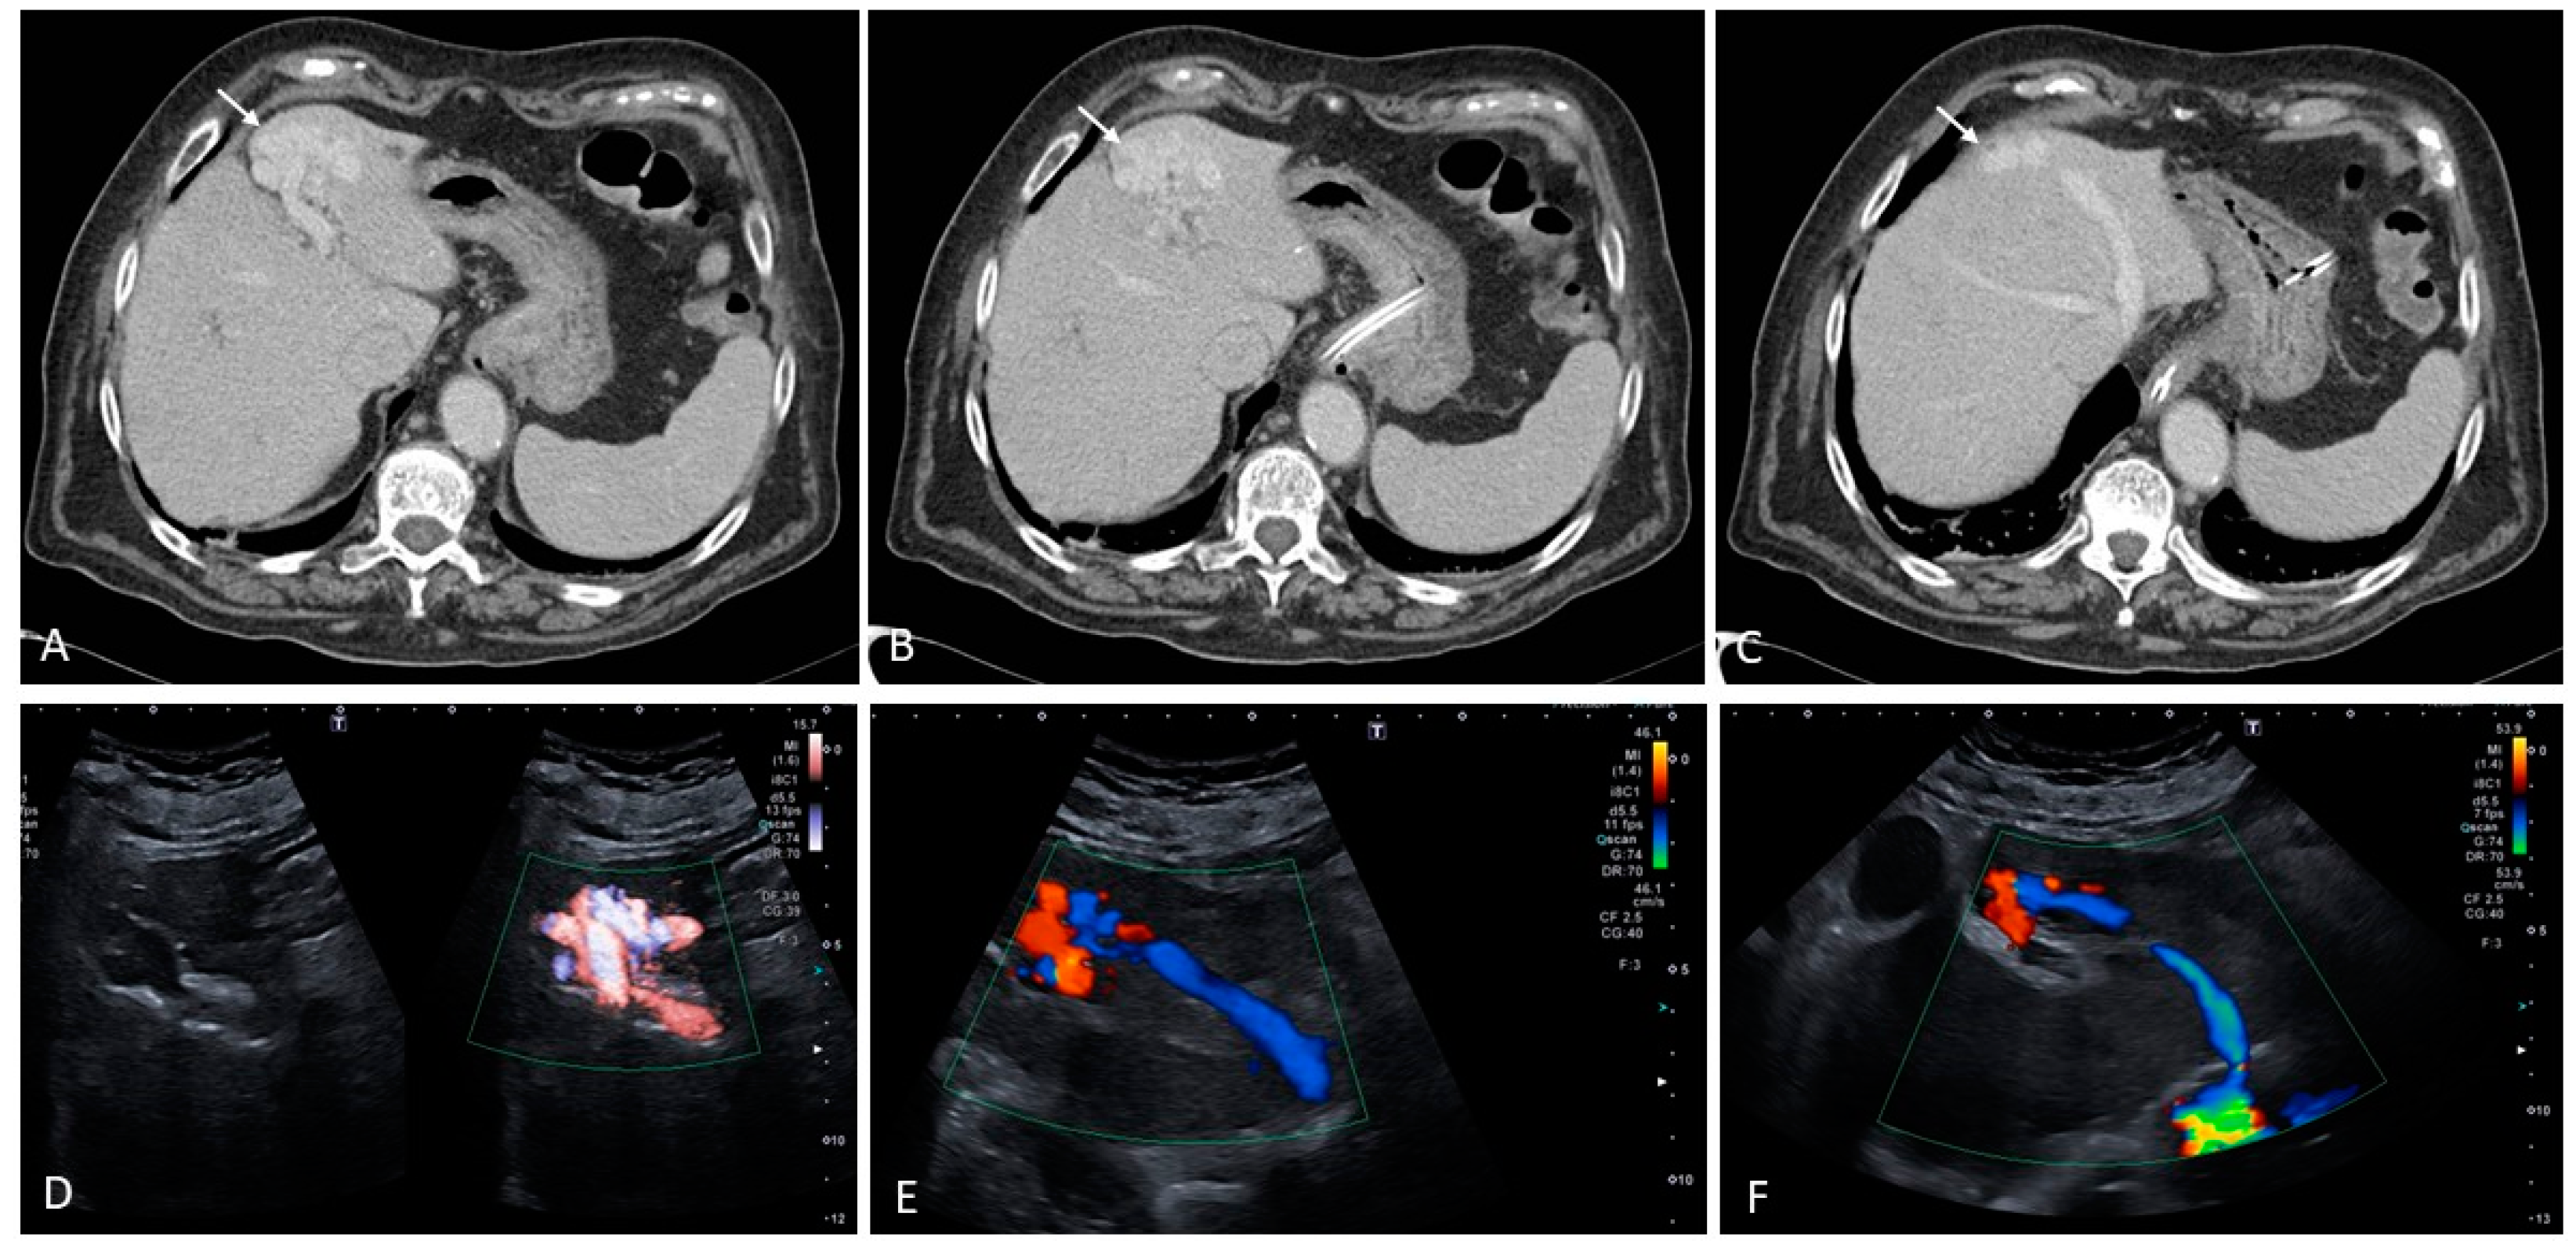

4.1. Budd–Chiari Syndrome

6. Vascular Malformations

- Hepatic artery dilatation > 4 mm.

- Normally, the diameter of the hepatic artery is smaller than that of the splenic artery; thus, an inversion of this relationship may be an early sign of liver VM.

- An increased velocity within the hepatic artery, with a peak flow velocity greater than 100 cm/s.

- Peripheral subcapsular ‘spots’ on power or color Doppler with high arterial blood flow velocities and low resistive indices are suggestive of small peripheral VMs.

- Other ultrasound findings include tortuous intrahepatic tubular structures communicating between the portal venous branches and the hepatic venous branches, tubular structures parallel to the portal branches representing dilated arterial branches, and vascular shunts. Arterio-systemic and arterio-portal shunts have low resistive indices, and arterio-portal shunts may be accompanied by the presence of portosystemic collaterals. Furthermore, arterio-systemic shunts can lead to arterialization, dilation, and turbulent flow of the portal vein and hepatic veins.